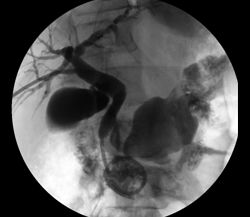

The third case illustrates percutaneous biliary drainage, which is the insertion of a drainage catheter from the skin, through the liver, into the duodenum, crossing the site of biliary obstruction. It is often the first step towards percutaneous biliary stenting and serves to decompress dilated biliary ducts and allow their inflamed walls to simmer down while waiting for the pathologic diagnosis of the obstructive disease before deploying a metallic stent across it. (Such staged approach is unnecessary if a non-metallic stent is employed in treating the disease, because such stents are easily retrievable should the final diagnosis recommend alternative forms of treatment; metallic stents, once deployed, are not removable.) Secondly, percutaneously stenting a biliary obstruction at the time of initial crossing is sometimes prolonged and challenging and risks seeding the blood stream with bacteria from the inflamed and friable biliary wall, causing sepsis.

In this woman, crossing her obstructed ampulla of Vater at ERCP failed, so I had to percutaneously deploy a biliary drainage catheter across it while waiting for the result of her biliary brushings. The single image illustrates the deployed catheter across the obstruction.